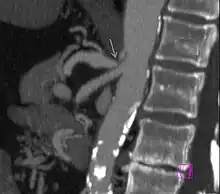

CT angiographic findings in MALS[2]

1. Focal narrowing of proximal celiac artery with poststenotic dilatation

2. Indentation on superior aspect of celiac artery

3. Hook-shaped contour of celiac artery

Further evaluation and confirmation can be obtained via angiography to investigate the anatomy of the celiac artery.[5] Historically, conventional angiography was used, although this has been largely replaced by less invasive techniques such as computed tomography (CT) and magnetic resonance (MR) angiography.[2][5] Because it provides better visualization of intra-abdominal structures, CT angiography is preferred to MR angiography in this setting.[5] The findings of focal narrowing of the proximal celiac artery with poststenotic dilatation, indentation on the superior aspect of the celiac artery, and a hook-shaped contour of the celiac artery support a diagnosis of MALS.[2] These imaging features are exaggerated on expiration, even in normal asymptomatic individuals without the syndrome.[2]

Proximal celiac artery stenosis with poststenotic dilatation can be seen in other conditions affecting the celiac artery.[2] The hook-shaped contour of the celiac artery is characteristic of the anatomy in MALS and helps distinguish it from other causes of celiac artery stenosis such as atherosclerosis.[2] This hooked contour is not entirely specific for MALS however, given that 10–24% of normal asymptomatic individuals have this anatomy.[2]